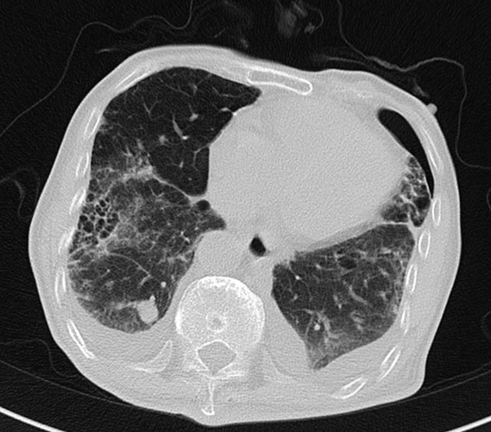

胸部CT回报:右肺间质性病变、双肺气肿、右上肺结节影、主动脉硬化、右侧胸膜钙化。

PET-CT检查:1、胃癌大部切除术后改变;肝左外叶近包膜下高代谢结节(于临近胃食管吻合口分界欠清),考虑肝转移。2、右肺中上叶多发结节伴代谢轻度增高;双肺间质纤维化;双肺泡性气肿;经根部气管憩室;贫血;动脉硬化;双侧胸膜增厚;右肺门及纵隔内多发淋巴结增生。

2020-01-08查胸部CT:双肺间质纤维化伴双肺气肿,双肺炎症,伴支气管扩张,右肺上叶结节样影,性质待定,双侧胸腔积液,纵膈多发肿大淋巴结,主动脉及冠状动脉硬化。

2020-08-31复查胸部CT:右肺结节影,结合病史考虑转移性病变,左侧局限性气胸,双肺气肿,双肺间质性病变,双侧胸腔积液;心脏增大,主动脉硬化。